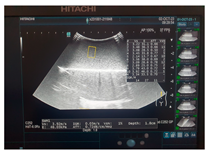

| Ultrasound | ![]() | ![]() | ![]() |